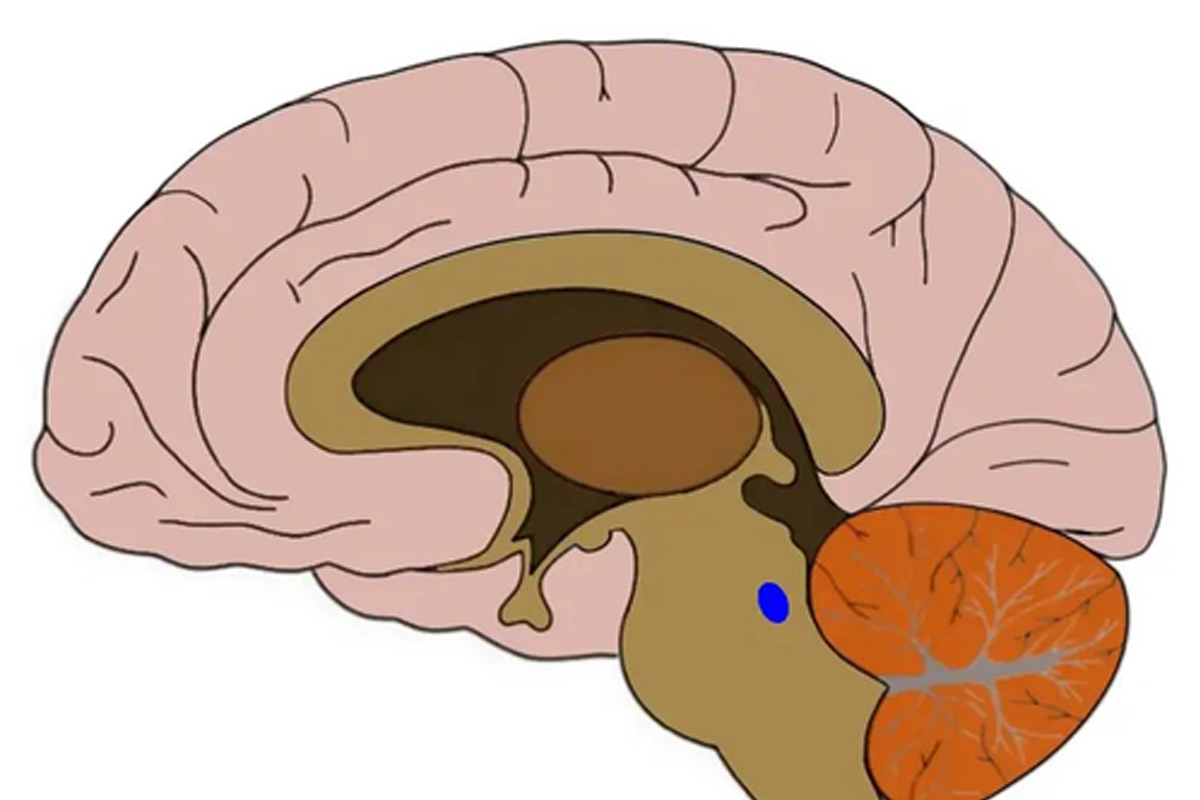

बेल्जियम में यूनिवर्सिटी ऑफ लीज की एक टीम ने अल्ट्रा-हाई फील्ड 7 टेस्ला एमआरआई का उपयोग करके प्रदर्शित किया कि हमारे आरईएम स्लीप (नींद का वह हिस्सा जिसके दौरान हम सबसे अधिक सपने देखते हैं) की गुणवत्ता लोकोस सेरुलियस की गतिविधि से जुड़ी है।

यह छोटा मस्तिष्क नाभिक, 2 सेमी लंबी स्पेगेटी के आकार का मस्तिष्क के आधार पर (ब्रेनस्टेम में) स्थित होता है।

लोकोस सेरुलियस - लैटिन में "नीला धब्बा" के लिए - ऑटोप्सी में देखे जाने पर इसका रंग इसके नाम पर होता है। यह नॉरएड्रेनालाईन नामक एक न्यूरोमॉड्यूलेटर को स्रावित करने के लिए मस्तिष्क के लगभग हर क्षेत्र (और रीढ़ की हड्डी में) में प्रोजेक्ट करता है, जो न केवल न्यूरॉन्स को उत्तेजित करने और उन्हें जगाए रखने के लिए महत्वपूर्ण है, बल्कि स्मृति, भावनात्मक प्रसंस्करण, तनाव और चिंता जैसी संज्ञानात्मक प्रक्रियाओं की एक पूरी श्रृंखला के लिए भी महत्वपूर्ण है।

प्रयोगशाला में एक शोधकर्ता और जेसीआई इनसाइट में प्रकाशित लेख के पहले लेखक एकातेरिना कोशमैनोवा ने कहा, पशु अनुसंधान पहले ही दिखा चुका है कि इस छोटे नाभिक का कार्य नींद और जागने के लिए आवश्यक है। "मनुष्यों में, बहुत कम सत्यापित किया गया है क्योंकि नाभिक का छोटा आकार और इसकी गहरी स्थिति पारंपरिक एमआरआई के साथ विवो में इसे देखना मुश्किल बनाती है।

7 टेस्ला एमआरआई के उच्च रिज़ॉल्यूशन के लिए धन्यवाद, हम नाभिक को अलग करने और जागने के दौरान एक साधारण संज्ञानात्मक कार्य के दौरान इसकी गतिविधि को निकालने में सक्षम थे, और इस प्रकार दिखाया कि हमारे लोकोस सेरुलियस जितना अधिक प्रतिक्रियाशील है, उतनी ही खराब नींद की गुणवत्ता और कम तीव्र हमारी आरईएम नींद है।